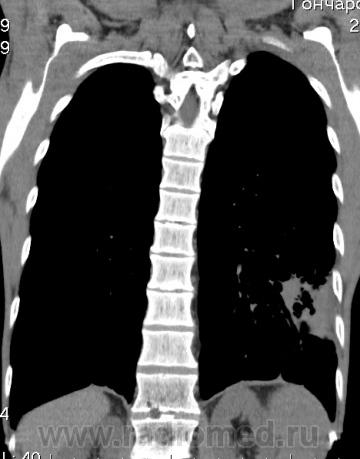

КТ - ОГК.  Ваше мнение коллеги?

На фоне консолидации полость без содержимого. Может быть всё что угодно, что сопровождается деструкцией. Нужны ещё томограммы в лёгочном окне.

Изображения выставлены все. Ваше мнение уважаемые коллеги?

Это КТ 2-летней давности и попало оно мне в руки, после недавнего прохождения контроля пациентом, когда мы стали перед вопросом о специфическом / не специфическом процессе.

Тогда, пациента 2 месяца лечили от пневмонии, лечили интенсивности, стационарно, в серьёзном учреждении.